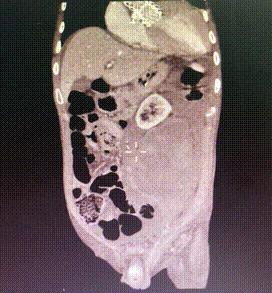

行急诊手术 腹主动脉及左侧股动脉造影

左侧股动脉见造影剂外渗

球囊压迫后植入覆膜支架

复查造影